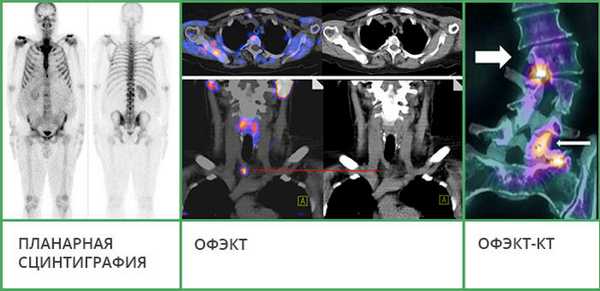

Существуют три основных способа проведения сцинтиграфии:

- Планарная сцинтиграфия – наиболее простая методика. Позволяет получать двухмерные снимки, как во время рентгенографии, на которых видно распределение радиофармпрепарата. Этот вид исследования часто используют, чтобы обнаружить в костях первичную злокачественную опухоль или метастазы.

- Однофотонная эмиссионная компьютерная томография (ОФЭКТ) позволяет получить серию смежных двухмерных изображений, на которых также визуализируется распределение радиоактивного индикатора.

- ОФЭКТ-КТ – наиболее информативная методика. Во время исследования данные сцинтиграфии совмещают со снимками, полученными с помощью КТ. Это позволяет получать трехмерные изображения, судить не только о патологических изменениях в костях, но и о точной локализации очагов.